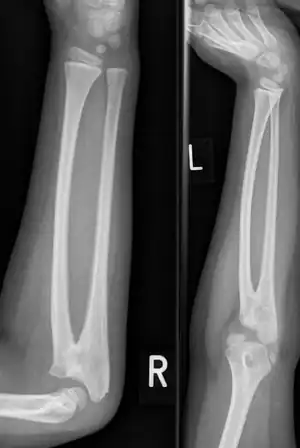

Sinostose radioulnar

A sinostose radioulnar é uma condição rara em que existe uma ligação anormal entre os ossos do antebraço rádio e ulna.[1] Pode estar presente no nascimento (congênito), quando é o resultado de uma falha na formação dos ossos ou após uma lesão (pós-traumática).[2]

Normalmente causa restrição de movimento do antebraço, em particular rotação (pronação e supinação), embora geralmente não seja doloroso, a menos que cause subluxação da cabeça do rádio.[1] Ela pode estar associada ao deslocamento da cabeça do rádio, o que leva à extensão limitada do cotovelo.[2]